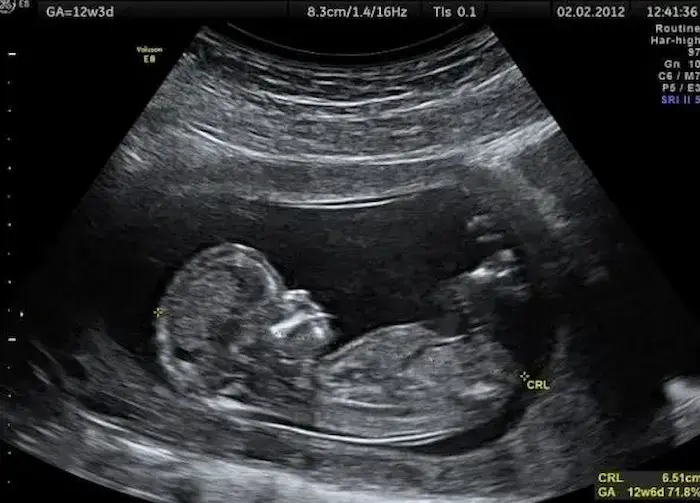

متى يظهر نوع الجنين في السونار رباعي الأبعاد؟

ينصحك بالخضوع لإجراء تصوير الموجات فوق الصوتية رباعية الأبعاد بعد الأسبوع الرابع والعشرين، حيث يكون الجنين أكثر نموًا، ويعطر صورًا أفضل.